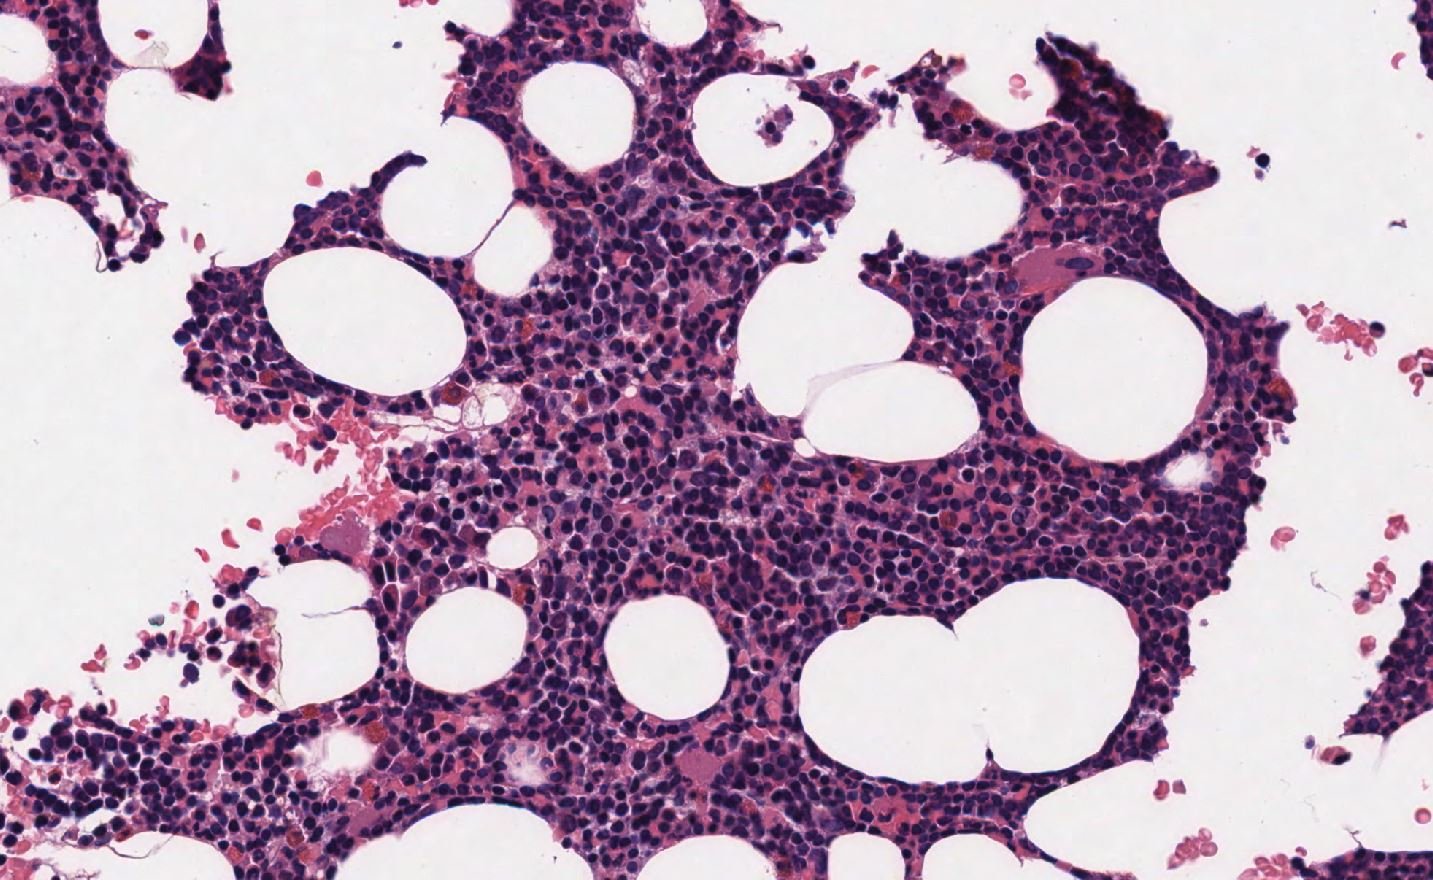

Case: BoneMarrow